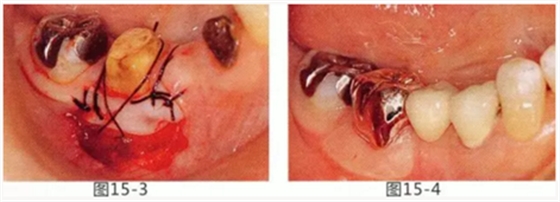

頰系帶延伸至游離齦,附著齦缺失的病例中,為了完成之后修復(fù)體能夠保持長(zhǎng)期清潔,將系帶切除,并通過(guò)FGG(游離齦移植)增加附著齦。

圖15-1,2 右下6近中部的頰系帶延伸到游離齦,附著齦也處于缺失狀態(tài)。如果在這個(gè)狀態(tài)下進(jìn)行修復(fù),會(huì)使清潔變得困難,容易引發(fā)牙齦萎縮。

圖15-3 切除系帶。為了獲得附著齦,進(jìn)行游離齦移植。

圖15-4 手術(shù)完成6個(gè)月后,佩戴修復(fù)體時(shí)的狀態(tài)。